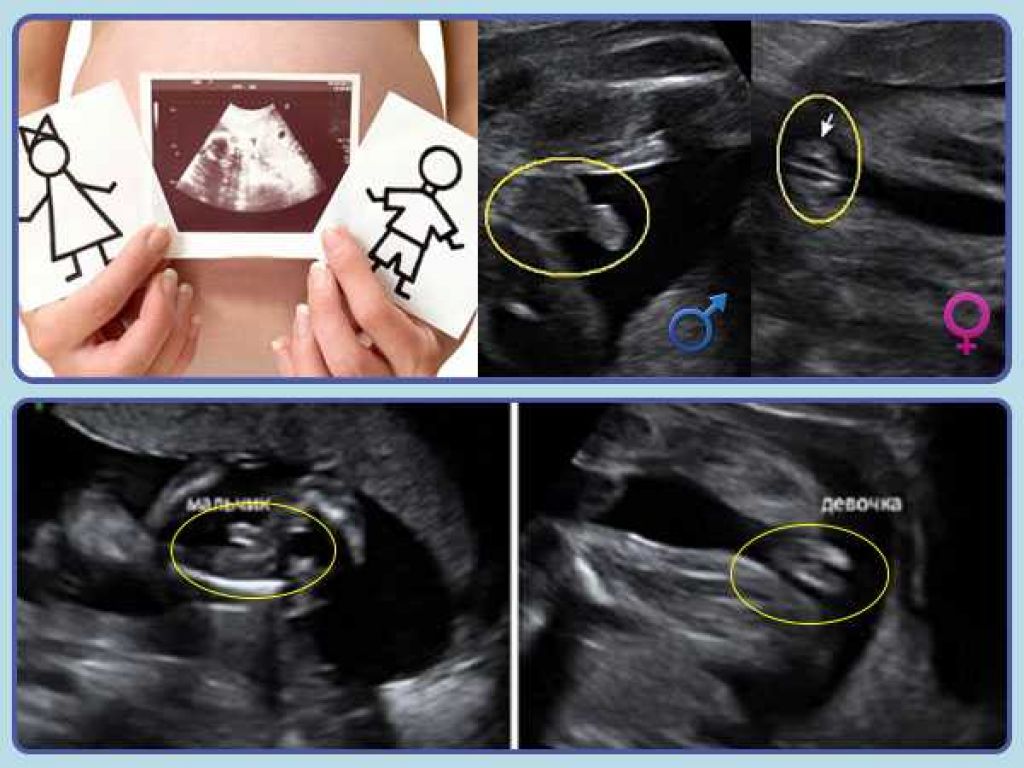

Пол на 14 неделе беременности по узи

Пол на 14 неделе беременности по узи 88 фото